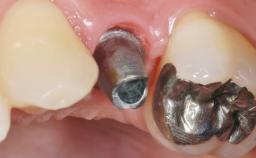

Early Placement of an Implant in a Maxillary Right Central Incisor Site

Abutment Type Customized

Prosthesis Type FDP

Retention Cemented, with prosthesis margin < 3mm submucosal Cemented, with prosthesis margin < 3mm submucosal

Provisional Implant-Supported Prosthesis Prosthodontic margin < 3 mm apical to mucosal margin Prosthodontic margin < 3 mm apical to mucosal margin